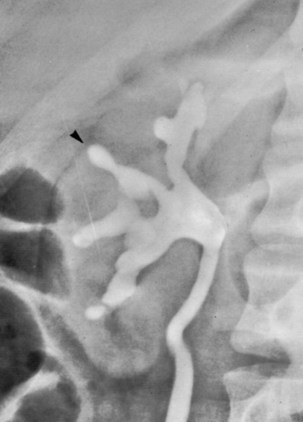

Chronic pyelonephritis describes a shrunken, scarred kidney, diagnosed by morphologic, radiologic, or functional evidence of renal disease that may be postinfectious but is frequently not associated with UTI. Bacterial infection of the kidney may cause a focal, coarse scar in the renal cortex overlying a calyx, almost always accompanied by some calyceal distortion (Fig. 10–1), which can be detected radiographically or by gross examination of the kidney. Less commonly, renal scarring from infection can result in atrophic pyelonephritis or generalized thinning of the renal cortex, with a small kidney appearing radiographically similar to one with postobstructive atrophy (Fig. 10–2).

Figure 10–1 Excretory urogram demonstrates focal, coarse scarring in the right kidney of an 18-year-old girl with a history of many recurrent fevers between 2 months and 2 years of age. A cystogram when the patient was 2 years old established an atrophic left kidney with marked reflux up to the left kidney and slight reflux up to the right kidney. Excretory urography at the age of 6 years established severe atrophy of the left kidney. She had no infections between the ages of 6 and 15 years. Several reinfections occurred at the age of 15 years, and they ceased with prophylactic therapy. Her blood pressure has remained normal, and her serum creatinine level was 0.9 mg/dL at the age of 18 years. At 21 years of age she stopped antimicrobial prophylaxis for 18 months without infections or introital colonization with Enterobacteriaceae. Note that all calyces are blunted and that one extends to the capsule (arrowhead) because of atrophy of the overlying cortex.